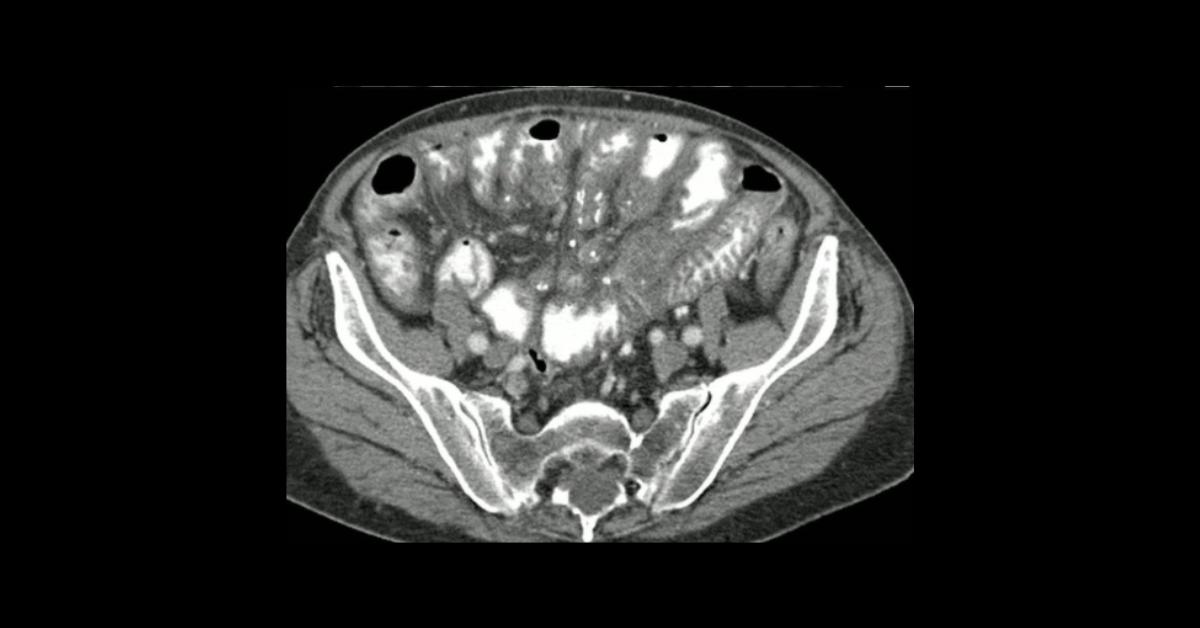

Presented by Ashish Khandelwal, MBBS, MD at Practical Radiology 2025. The main objectives of this talk are to understand types and etiopathogenesis of bowel ischemia, recognize imaging manifestations with special emphasis on early diagnosis and differentials and learn management principles relevant to imaging.

1. Understand types and etiopathogenesis of bowel ischemia

2. Recognize imaging manifestations with special emphasis on early diagnosis and differentials